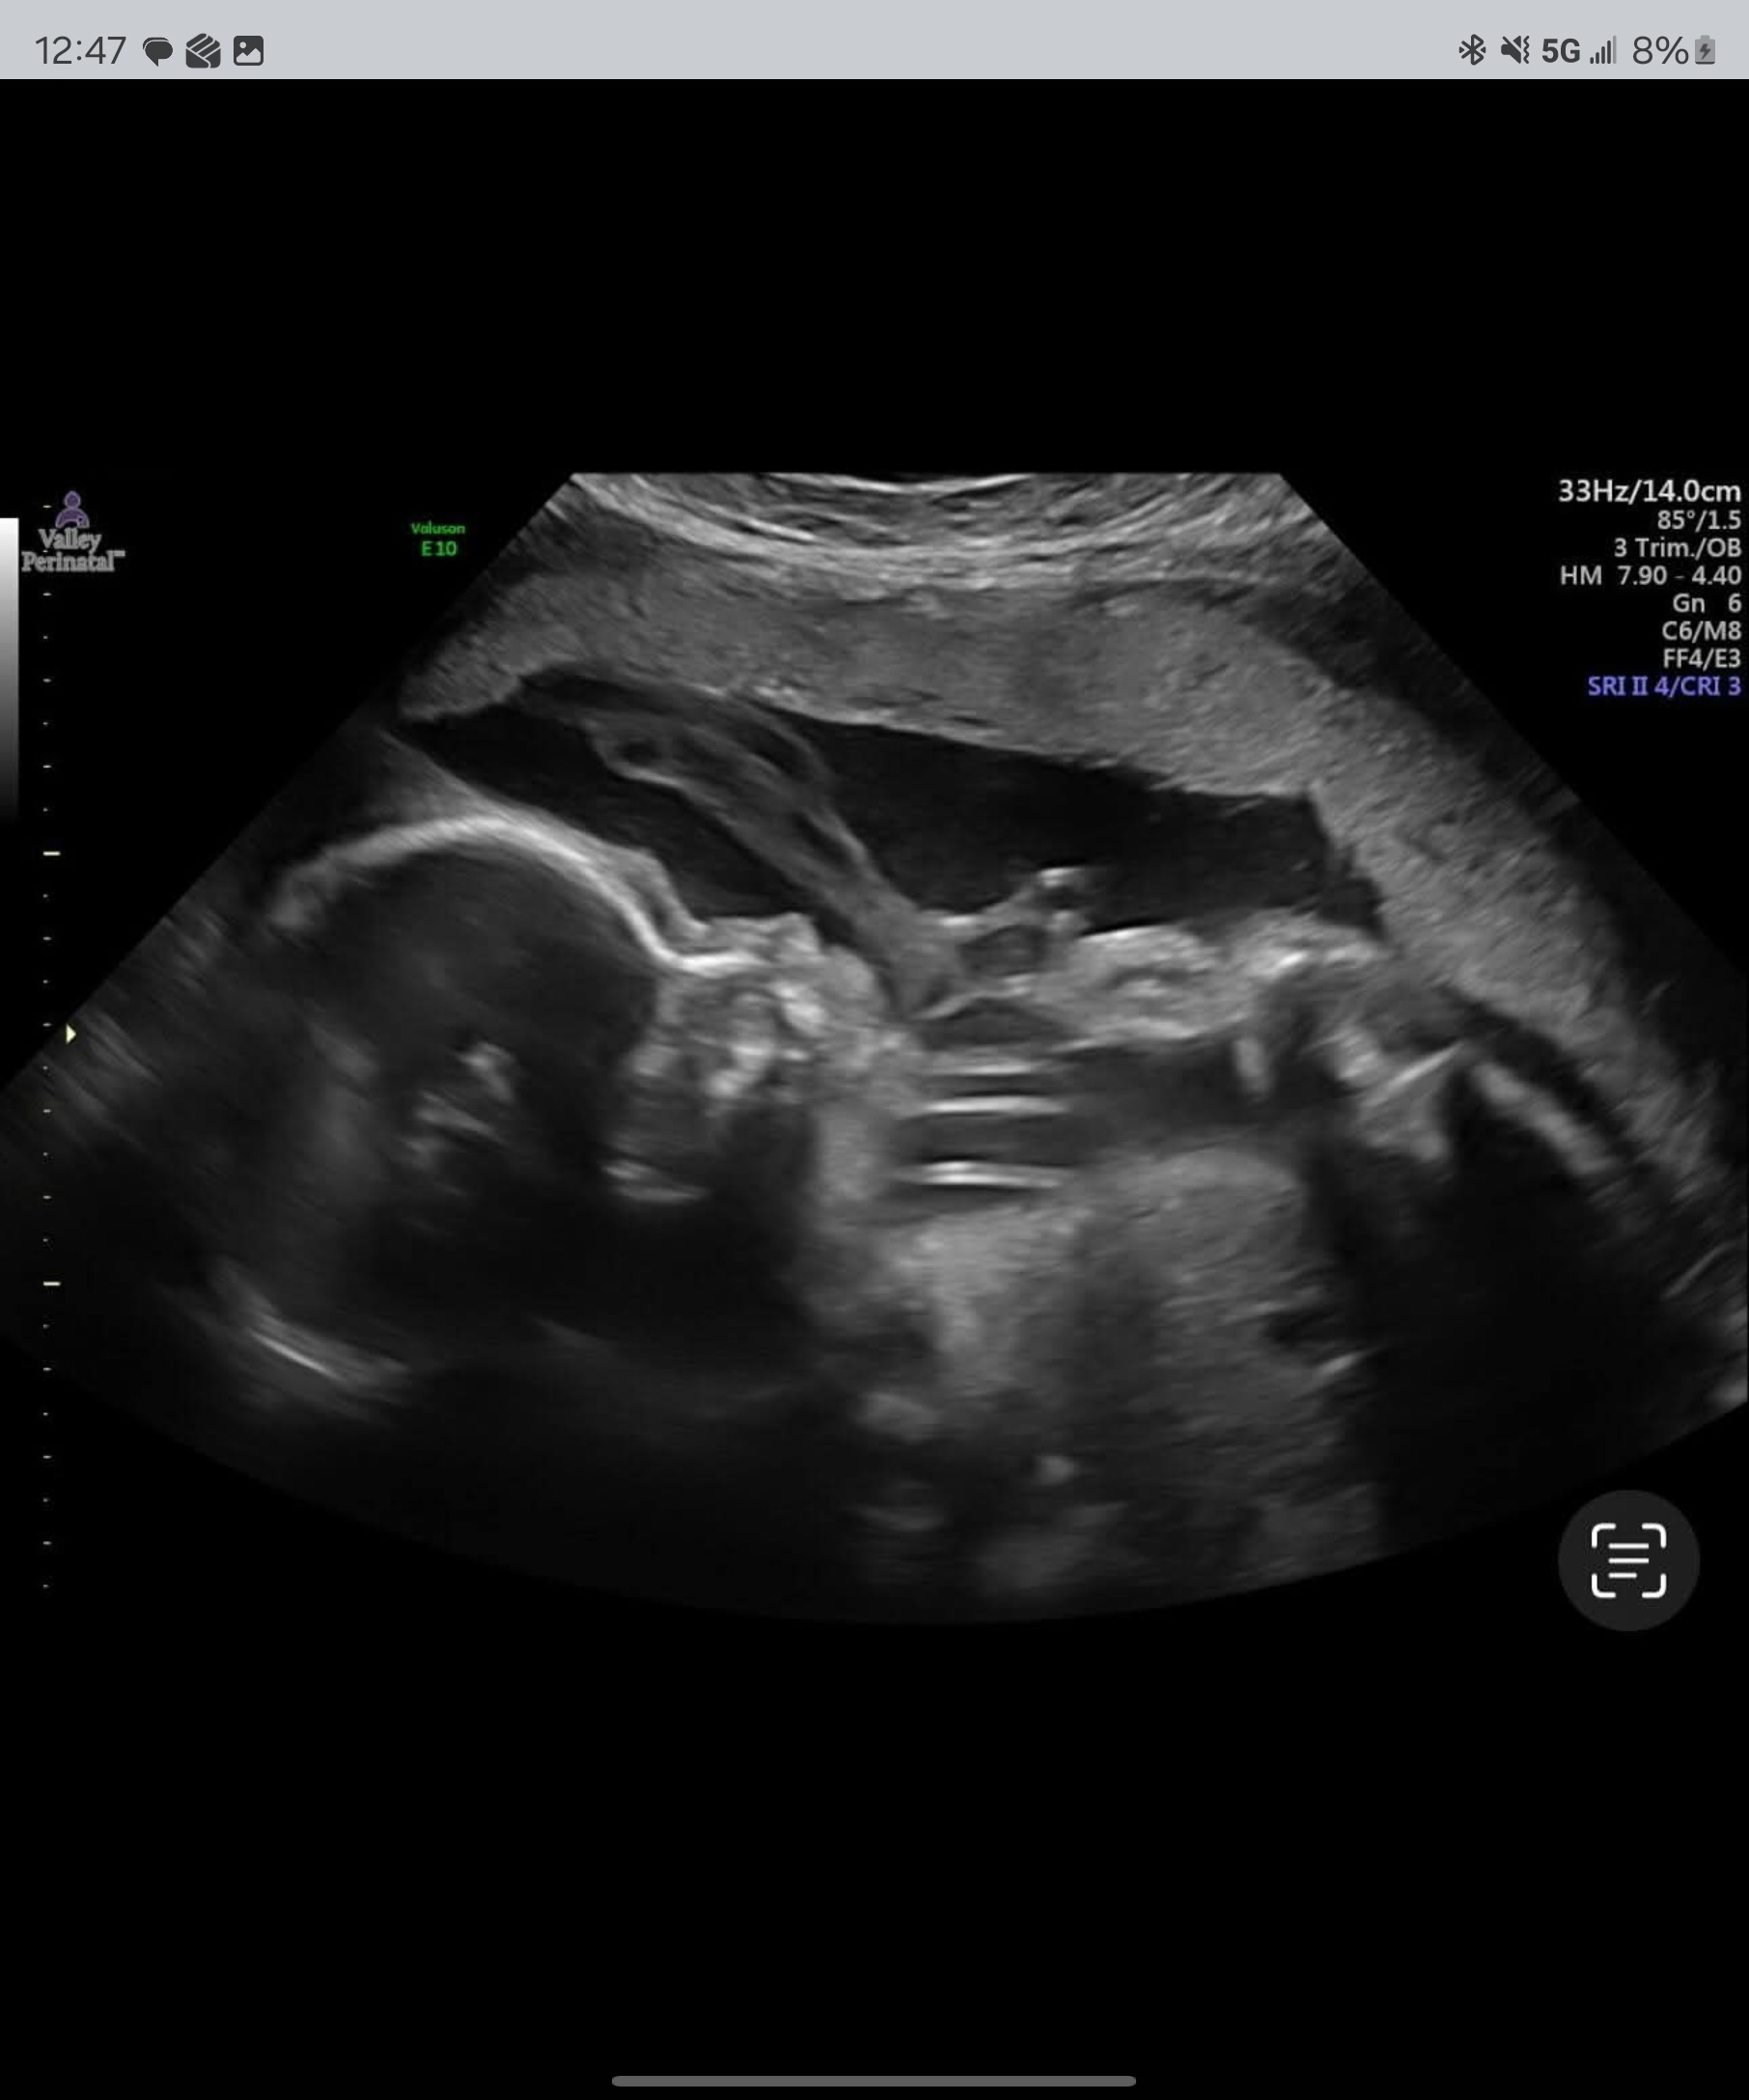

My name is Terry, and I’m the father of a brave young woman named Jewel. She is 25 years old, newly married, and 27 weeks pregnant with her first child — my future granddaughter.

But Jewel is also pregnant.

Jewel chose to forgo chemo right now, risking her own life so her baby could be safe.

She put her daughter’s life above her own.